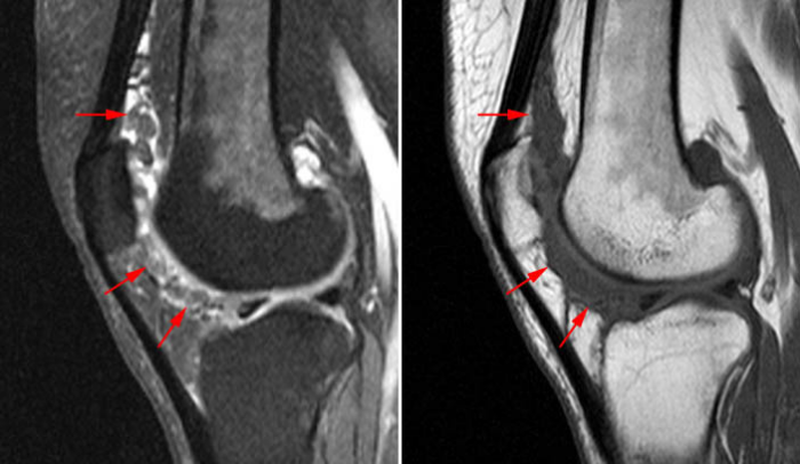

7ИЮЛОсновные возможности проведения процедуры МРТ коленного суставаСписокфирмНезависимо от возраста человека именно колено считается одним из самых травмируемых суставов в теле.